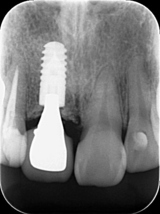

正確で安全なインプラント手術 低価格で高品質 安心の10年保証(条件なし)

安心・安全なインプラント手術の成功の鍵は、CT撮影によるCTデータと口の中のデータのマッチングです。このシュミレーションで作成されたサージカルガイドを使用することで、さらなる安全性の向上が得られます。

●熟練した歯科医師の経験と技術で手術時間の短縮(早ければ5分から10分)、患者負担の軽減

●骨の厚みはもとより、神経・血管の位置や走行まで全ての角度から把握できる

●事前に安全な治療計画が立てられ、精査できる

当院では、インプラント相談、CT撮影、診断、サージカルガイド、メインテナンス(定期検診)は、全て無料です。

インプラントは、世界シェアナンバー1のストローマン使用、このインプラントは、今まで4~6ヶ月かかっていたものが

3週間と超最短で骨とくっついてしまうのが、最大の特徴です。

上部構造(被せ物)は100%ネジ止め固定です。

セメント固定ではないので、適合がよく、急な脱落(歯が外れる)のリスクもありません。